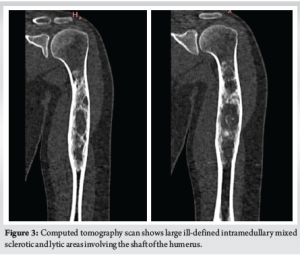

A 22-year-old female patient presented with complaints of pain in her left arm on and off for the past 2 years, which had been aggravated over the last 1 month. Pain is an insidious, progressive, non-radiating, dull aching type, aggravated on physical activity, relieved on rest. Patient had an alleged history of trauma 6 years back (skid and fall at her residence) sustaining injury to left arm and diagnosed to have a humerus fracture and lytic lesion. For which she was treated conservatively at an outside hospital. After 2 months of the fracture, the patient sustained again fracture over the same site and opted for conservative treatment. After 2 months of refracture aspiration (~50 mL) under CARM Guidance at SBMCH was done. On examination, no scar, sinus, or obvious swelling was noted. No soft tissue/bony tenderness seen. Range of motion (shoulder and elbow) was full and free without distal neurovascular deficit (DNVD). Blood investigations were carried out and found to be normal. X-ray (Fig. 1) showed mixed ill-defined lytic expansile lesions with a narrow zone of transition over the proximal 2/3rd of the left humerus. After the surgical procedure, the curettage bone was sent for histopathology (Fig. 2) and reported as fungal infection.

This case was reported due to its rarity and diagnostic complexity. While fibrous dysplasia is a known benign lesion with distinct radiological features, this case demonstrates that fungal infections can closely mimic such lesions both clinically and radiographically. The unexpected histopathological finding of fungal spores in an immunocompetent patient underscores the importance of maintaining a broad differential diagnosis when evaluating bone lesions. The incidence of fungal infection of bones and joints is usually low and rare. Invasive fungal infections are more likely to be associated with a rising population of immunosuppressed patients [7], and are also seen in patients with several comorbid conditions. Patients under steroid treatment are likely to be immunosuppressed and are prone to acquiring infections. Species such as Candida and Aspergillus are the most common causative organisms [8]. Candida, being an endemic dimorphic fungus, is accountable for an enormous number of cases globally. Fungal infections are commonly transmitted through the hematogenous route. Transmission from contiguous infection, or by direct inoculation following trauma or surgery, is also noted. Clinically, adults present with mild features, often without fever or a rise in inflammatory markers. Children may have features of vertebral osteomyelitis, which differ from adult presentations [9]. Due to the dormant nature of symptoms in adults, diagnosis is often delayed. Diagnosis is based on tissue culture, tissue histology, and clinical correlations. In this case, the X-ray findings (Fig. 1, 2) mimicked fibrous dysplasia, showing a mixed expansile lesion with ground-glass opacity. The patient was clinically and radiologically (Fig. 3-5) diagnosed to have fibrous dysplasia. However, histological examination revealed a fungal infection. Therefore, to avoid misdiagnosis, tissue culture and histology are necessary in similar presentations. Once diagnosed, appropriate antifungal medication and often surgical debridement are required.

Fibrous dysplasia is characterized by the replacement of mature bone marrow with an immature abnormal matrix by fibro-osseous growth. Due to somatic mutation, it affects woven bone and leads to failure of turning into lamellar bone [10]. This condition often has no symptoms and is an incidental finding, usually presenting as a pathological fracture. Radiographically, a clearly circumscribed lesion with a narrow zone of transition can be appreciated. Computed tomography and magnetic resonance imaging (Fig. 3-6) are also found to be useful. Fibrous dysplasia is mostly treated symptomatically – such as managing pathological fractures or with simple palliative care [11,12]. Curettage, bone grafting, and fixation techniques are also used for the correction of deformities. Medically, bisphosphonates may be supplemented with other supportive treatments.